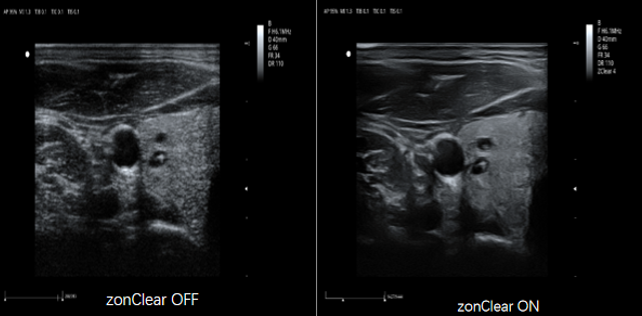

ZClear 自适应空域滤波技术

具有先进的自适应空域滤波,并与运动补偿时域滤波技术相结合,通过探测解剖结构边界位置有效降低斑点噪声,大幅增强组织边界显示能力和组织回声显示能力,增强临床诊断信心。